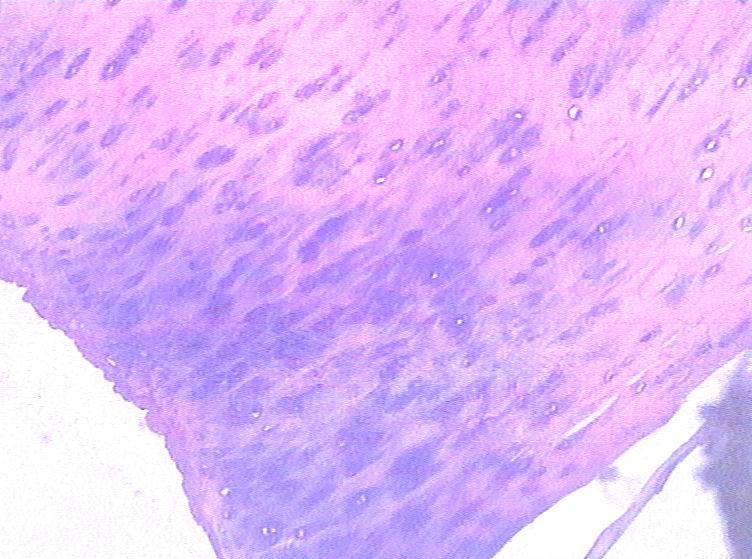

男,48岁,肿块直径1.5CM。

肿块位于何处,就楼主所给图片无分叶状结构,无粘液样基质,无双核软骨细胞无核异型,不符合软骨肉瘤,应该是个良性病变。

高疑软骨肉瘤,请同行会诊。

请传X线片及详细的临床资料。这些图像不足以诊断恶性。